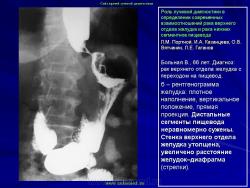

Возможности новых технологий

В арсенале современной лучевой диагностики рака желудка имеются средства, позволяющие внести ясность в случаях, когда возникает расхождение рентгенологического и эндоскопического заключений. Эндоскопия, являясь великолепным методом диагностики, не всегда может ответить на все интересующие клиницистов вопросы, и с учетом неуклонного роста диффузных и смешанных раков ее возможности в выявлении рака желудка все же ограничены. Здесь следует более четко обозначить важную возможность проведения дообследования. Речь идет о так называемых новых технологиях. Лучевая диагностика, обогатившись такими методами, как УЗИ, КТ и МРТ (а это особенно важно при сегодняшней ситуации с раком желудка), может в отдельной клинической ситуации дополнить имеющуюся диагностическую информацию. При этом важно отметить, что классическая рентгенология получила за последнее время свое весьма существенное развитие и ее по-прежнему следует считать основным способом выявления рака желудка. По прошествии вот уже более 25 лет активного изучения возможностей так называемых новых технологий лучевой диагностики настало время дать им объективную оценку.

Безусловно, каждый из этих методов в определенных конкретных ситуациях, учитывая произошедшую перестановку акцентов в морфологии рака желудка, может внести существенный вклад в его диагностику. Однако основные достоинства каждого из этих методов связаны с возможностями с их помощью уточнить вопросы протяженности опухолевой инфильтрации по стенкам желудка, а также распространенности процесса на соседние органы и ткани брюшной полости и забрюшинного пространства. Это особенно ценно, если учитывать, что сегодняшний рак желудка, за очень редким исключением, резко затрудняет определение истинной протяженности даже при проведении радикальной операции. И тем не менее, выделяя современные возможности традиционного рентгенологического раздела в качестве основной базы выявления рака желудка при лучевом исследовании, мы все же считаем необходимым выделить некоторые принципиальные положения методико-семиотических основ и новых технологий лучевой диагностики рака желудка.

Вопросы применения каждого из этих дополнительных методов не следует рассматривать по принципу "от простого к сложному". Точно также нельзя их считать и своеобразной диагностической необходимостью. Наш опыт длительного общения с этими новыми технологиями все больше убеждает в том, что чем выше профессионализм лучевого диагноста, проводящего рентгенологическое исследование желудка, тем в меньшей степени возникает необходимость применения этих высоких технологий для уточнения наличия опухолевой инфильтрации стенки желудка. Естественно, в тех случаях, когда с помощью неоднократно проведенной эндоскопии, с взятием множественной биопсии (6, 8, 10 и более биоптатов) из участка утолщенной стенки желудка, выявленной при традиционном рентгенологическом исследовании, не удается гистологически верифицировать диагноз, применение УЗИ, КТ или МРТ является диагностической необходимостью. Но каждый из них имеет свои точки приложения: УЗИ с возможностью определения пятислойной структуры стенки желудка предпочтительнее для изучения дистального отдела и нижней половины тела желудка; КТ - для верхней половины тела и проксимального отдела желудка, а также дистальных сегментов пищевода; МРТ - для всех отделов желудка в особых случаях, так как оценка МР-сигнала, основанного на биохимической структуре ткани, может быть тем решающим фактором, который позволит принять решение в пользу проведения радикального оперативного лечения. В таких случаях они нужны для подтверждения инфильтрации стенки желудка, найденной при традиционном рентгенологическом исследовании. При этом важно отметить, что каждый из этих методов сохраняет свои ранее изученные возможности в диагностике рака желудка: распространенность процесса на соседние органы и ткани, выявление метастазов, прежде всего в печень, лимфатические узлы брюшной полости и забрюшинного пространства.